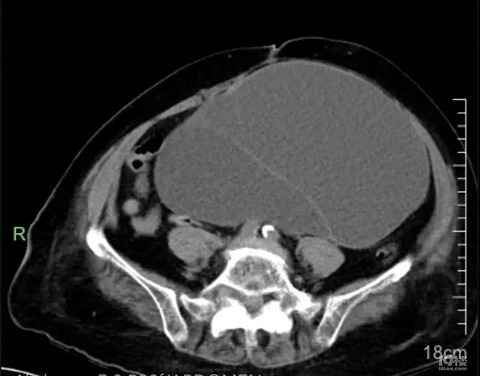

百岁老人肚子鼓出大包,我院妇科成功“拆弹”

我院妇科成功为百岁老人切除盆腔巨大肿物 “我真是做梦也没想到,妈妈一百多岁了,做完手术竟然可以恢复得这么好,太感谢你们了!”近日,我院妇科病房里,张奶奶(化名)的儿子握着医生的手激动地说道。 前不久,张奶奶肚子上凸起了一个大肿块,并且腹痛腹胀持续了数周,饭也吃不下,大小便也不好,眼看着人越来越虚弱了。家人送来我院就诊,全腹部CT检查发现张奶奶的腹盆腔里有个囊实性肿块,接近19cm×18cm大小,